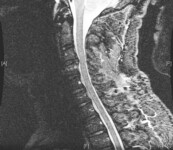

Doença degenerativa da coluna cervical

Alterações graves e de múltiplos níveis da doença degenerativa do disco, mas sem compressão significativa da medula espinhal (isto é, sem deformações ou alterações intrínsecas em T2) na ressonância nuclear magnética (RNM) cervical (T2 sagital)

Dennis A. Turner, MA, MD